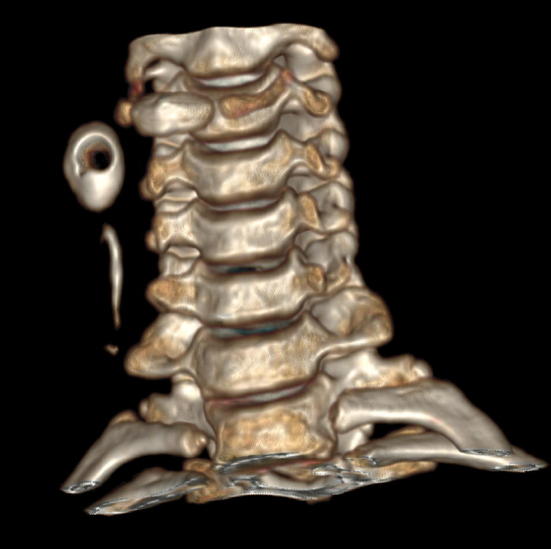

A 11 year girl presented with history of discharge from a tiny spot on the right side of the neck on and off since birth. There is no history of trauma or surgical intervention. Local examination revealed a small punctum on right side of neck on the medial border of the sternocleidomastoid muscle and lateral to right thyroid lobe. Thin watery fluid was oozing on pressure over the region. There was no sign of inflammation around the opening. CT sinography was performed to delineate the exact course of tract before surgery. Coronal and sagittal reformatted images revealed a contrast filled tract coursing anterior to right of sternocleidomastoid muscle and ending into the branchial cyst. The opacified cyst was crescentic in shape anteriorly showing a rounded unfilled isodense oval area in the dependent portion (Fig. 1). The isodense solid component of the cyst may be due to inspissated secretions lying in the dependent region. An air pocket was noted gravitating superiorly which was introduced inadvertently. These features were demonstrsated in 3D reformation as a concavo convex density (Fig. 2). Based on the imaging and clinical history, a diagnosis of branchial fistula in association with branchial cyst of second arch was considered. The patient underwent excision of the tract by a step ladder approach.

Fig. 1.

a–d CT scan sagittal and coronal views. a Coronal view shows Gd-DTPA opacified course of the branchial sinus tract. b, c Sagittal and axial views reveal the curvilinear branchial cyst with the dependent solid component. d Inadvertent introduction of air pocket is seen within the cyst